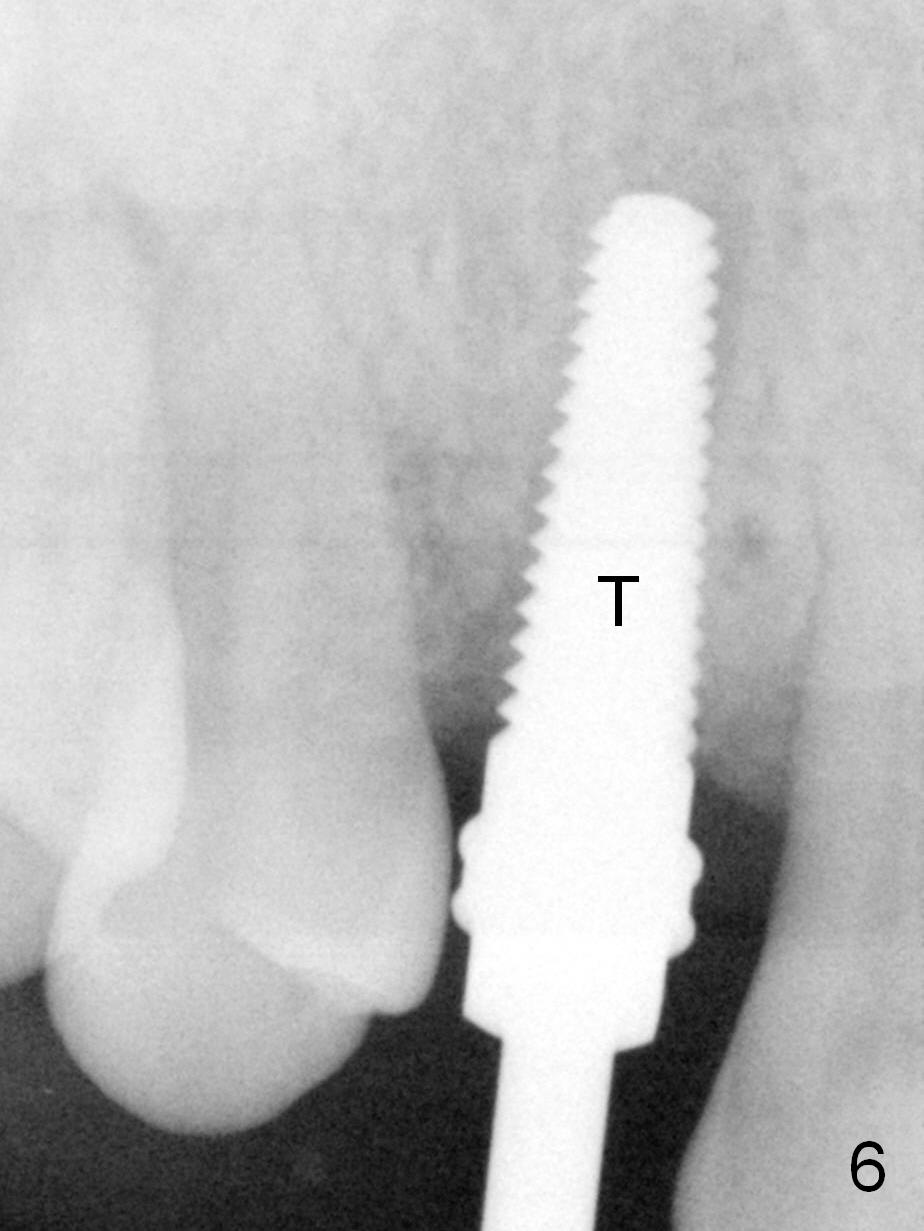

Four months post implant placement, the immediate provisional (Fig.1 P) has mobility with tenderness and perforation at the cervix (^). When the provisional is removed, the buccal plate bulging is more evident (Fig.2 arrowheads). The latter is apparently caused by bone expansion associated with implant placement (Fig.3 black *), since the bulging is not so obvious in a preop CBCT 3 D image (Fig.4 *). There is a layer of fiber granulation tissue (Fig.3 white *) around the mobile implant (I). More fiber tissue is noted when the implant is removed (Fig.5). A new osteotomy is created in the palatal wall of the existing implant site with 2 mm pilot drill, followed by 2.5 and 3 mm reamers. As a 4.5x17 mm tap is being inserted (Fig.6 T), it is deviated buccally. Reamers are re-used to try to remove more palatal bone to let the implant be placed more palatally. When a 4.5x17 mm tissue-level implant is placed (Fig.7,8 I with insertion torque >60 Ncm), there is a small buccal gap (Fig.8 *). A 20° angled abutment (Fig.7,8 A) is placed. An immediate provisional is fabricated with cosmetic satisfaction.